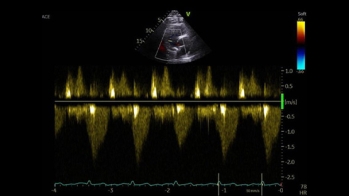

Différence entre amylose AL et ATTR, symptômes extra-cardiaques… Les signaux qui doivent conduire à suspecter une amylose revus par le Dr Antonin Trimaille et le Pr Nicolas Lamblin, dans le 1er épisode de la série “Amyloses cardiaques, les situations cliniques du cardiologue en formation”.